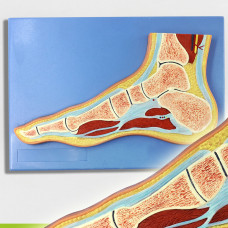

Life size Advanced Human Foot Joint Muscle Skeleton Sagittal Section Model

Highly detailed to show the structures of human foot & ankle joint skeleton, muscle, nerves, blood vessels, etc.

Ideal for professional teaching/study of human anatomy

Size: Life size

Material: High quality PVC

Foot Section Model, Life Size